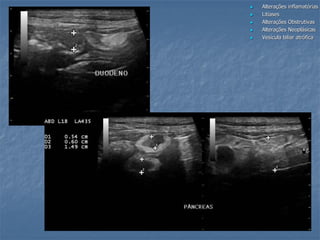

estômagoduodeno

DBC

duo

“plugs” no ducto biliar comum em gatos

Sem presença de sombreamento acústico

Remoção cirúrgica: concreções sólidas

Análise bioquímica: bilirrubina e colesterol